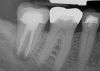

Treatment of combined endodontic and periodontal lesions does not differ from the treatment of either an endodontic lesion or a periodontal lesion. The part of the lesion sustained by the root-canal infection can usually be expected to resolve after proper endodontic treatment. Timing of the completion of the root-canal therapy, medicaments used, and assessment of restorability are considerations for the long-term success and survival of the tooth.7 Figures 7, 8, and 9 represent the timing of completion and restorative decision-making to complete all therapies.

In Figure 7, the periapical radiograph identifies the presence of the combined endodontic-periodontal lesion developing due to a carious lesion beneath an existing vintage gold crown with ill-fitting margins. Intraoral examination revealed a fistula developing and moderate pain on percussion and mastication. After occlusal access and clear visualization of the canals, the canals were shaped using the rotary files, with precautions taken not to perforate or enlarge the apical foramen. Maintaining the endodontic therapy within the canals prevents the infection from being introduced into the surrounding periodontium. In this case, calcium hydroxide medicament was placed into the canals and evaluated 30 days postoperatively.8

The patient returned for final evaluation of the provisional calcium-hydroxide endodontic therapy and resolution of the infection (33 days postoperatively). Fistula was not present; the tooth was not sensitive to percussion or mastication. The gold crown was removed using a high-speed metal cutting bur, the remaining caries were excavated conservatively, and the endodontic therapy was completed. Placement of glass-fiber reinforced composite and composite core buildup took place. The natural tooth structure to receive the glass-fiber post and a long-term restoration was available (Figure 8). Within one appointment, the tooth was restored (Figure 9). The patient was instructed to return for clinical and radiographic evaluation after 6 to 12 months to determine progression of periodontal healing. At that time, if the healing were adequate and the tooth were stable, evaluation of the tooth would be considered every 3 to 4 years.7

Fig 7. Primary endodontic and secondary periodontal lesion, mandibular second molar.

Figure 7

Fig 8. Gold crown removed, dentin excavated, canals shaped and filled.

Figure 8

Fig 9. 33 days postoperative fiber-post placement and CAD crown.

Figure 9